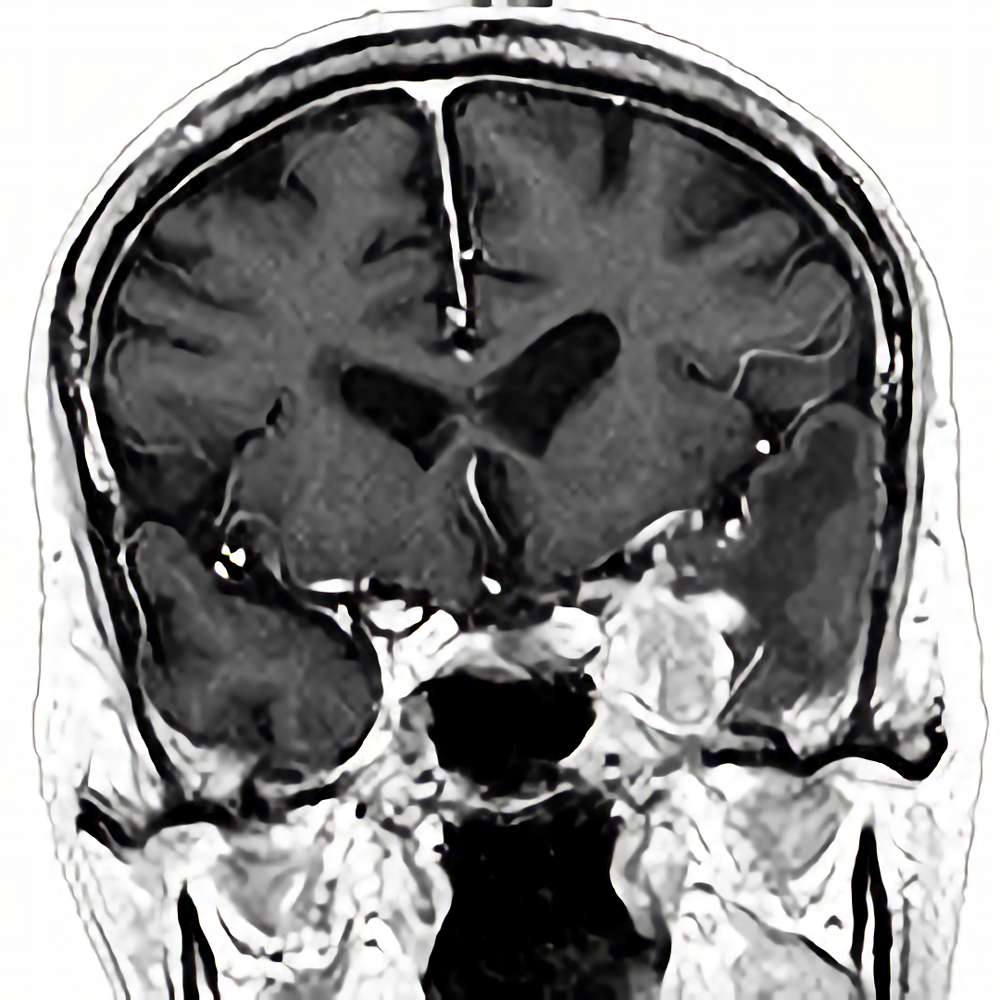

開頭症例

画像